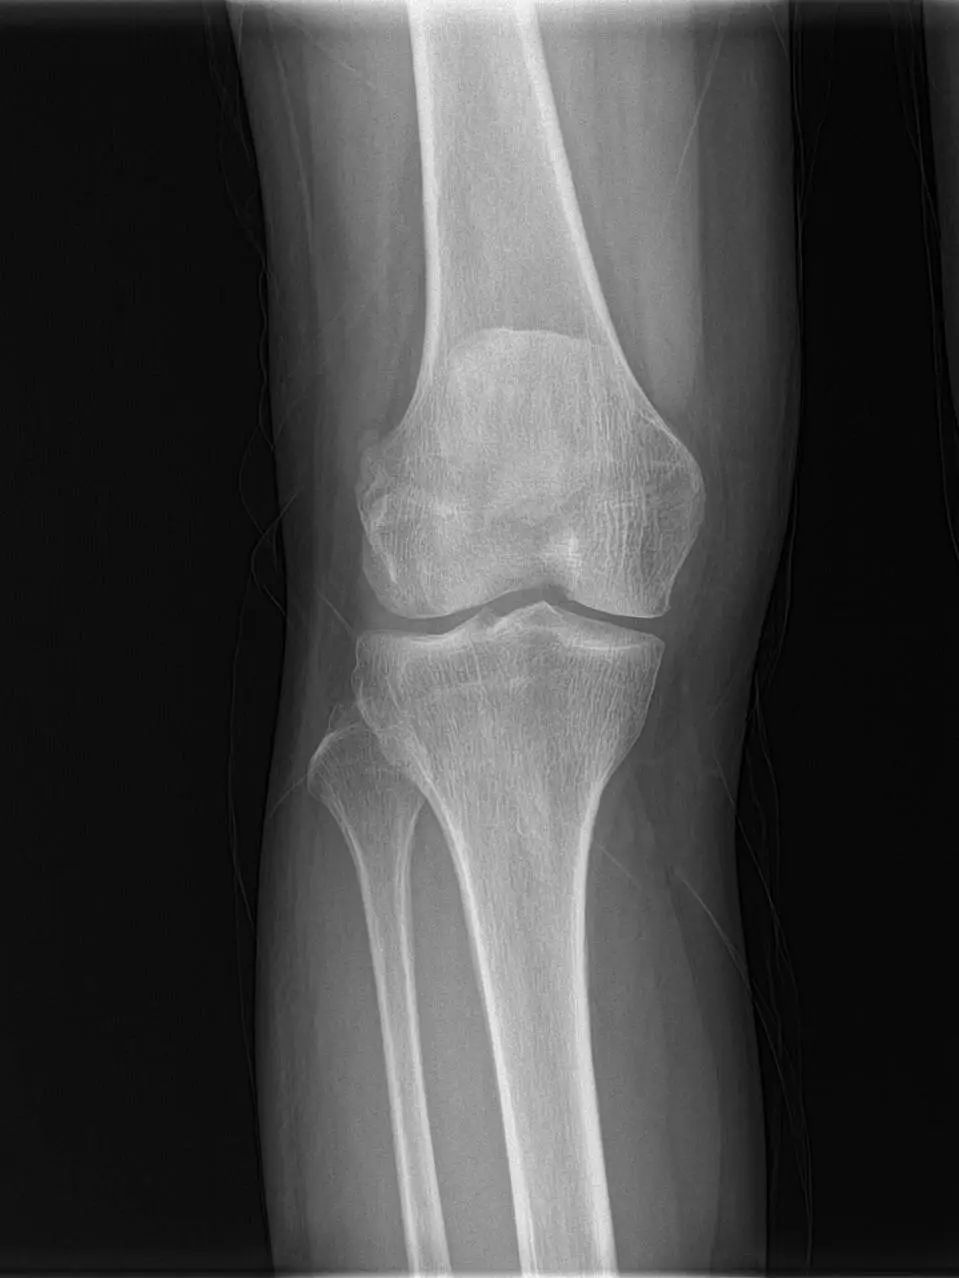

74岁的吕阿姨膝关节疼痛10余年,屈伸活动受限,外院就诊止痛药等保守治疗效果欠佳,拍片提示膝退行性骨关节炎。近日,她慕名来到上海市同济医院骨关节外科中心程飚主任门诊,程飚主任结合患者症状,影像学结果,体格检查,发现吕阿姨主要问题集中在膝关节内侧及髌股关节,膝关节外侧尚可。

为尽可能保留吕阿姨关节,程飚主任对定对吕阿姨进行膝关节部分置换手术,包括膝关节内侧单髁置换,髌股关节表面置换,尽可能减少膝关节截骨量,尽快恢复膝关节功能。吕阿姨术后第一天就开始下地走路了,她表示膝关节疼痛明显缓解,膝关节的活动范围也明显增加了,对程主任精准的手术治疗表示衷心的感谢。